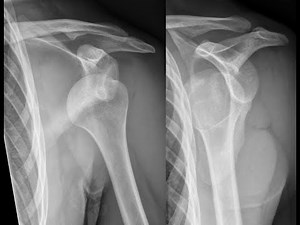

- Kocher Shoulder Reduction

Method Shoulder Reduction - Kocher